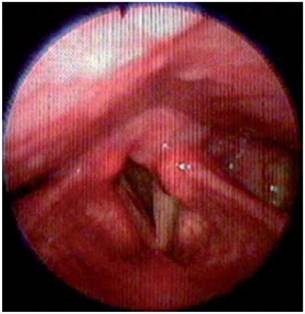

<p>Los estudios de hemograma, nitrógeno ureico, creatinina, glucemia y electrolitos se encontraron dentro de los rangos normales, el perfil lipídico mostró: colesterol total 160 mg/dl, colesterol HDL 50 mg/dl, colesterol LDL 89,8 mg/dl, triglicéridos 101 mg/dl. La tomografia de cráneo simple no mostró sangrado ni signos de isquemia. Se realizó una resonancia magnética cerebral simple que permitió evidenciar en las secuencias de T2 y FLAIR <italic>(Fluid Attenuation Inversion Recovery)</italic> una zona de hiperintensidad de señal a nivel del bulbo raquídeo en la región dorso-lateral caudal izquierda que es hipointensa en T1 (<xref ref-type="fig" rid="f1">figuras 1</xref>,<xref ref-type="fig" rid="f2">2</xref>,<xref ref-type="fig" rid="f3">3</xref>,<xref ref-type="fig" rid="f4">4</xref>). En la secuencia de difusión se observa restricción de la misma en la zona descrita con fenómeno de pseudonormalización al igual que en el mapa ADC <italic>(Apparent Coefficient Diffusion}</italic> (<xref ref-type="fig" rid="f5">figuras 5</xref>,<xref ref-type="fig" rid="f6">6</xref>). Los anteriores hallazgos se interpretaron como compatibles con un infarto bulbar lateral izquierdo.</p>

<p>El paciente paulatinamente presentó mejoría de la visión borrosa y principalmente de la disfagia y vértigo, hacia la semana siguiente ya podía alimentarse sin dificultad y mejoró la fuerza del hemicuerpo izquierdo completamente. Se dio egreso del hospital solo con leve disfonía, anhidrosis hemicara izquierda y marcha atáxica leve lográndose desplazar con bastón. En el seguimiento, luego de 1 y 3 meses posterior al inicio de los síntomas, el paciente retornó a su estado funcional previo y solo persistió con disfonía, la cual se explicó por la parálisis de la cuerda vocal izquierda que se confirmó por estudio de nasofibrolaringoscopia (<xref ref-type="fig" rid="f7">figuras 7</xref>,<xref ref-type="fig" rid="f8">8</xref>). El paciente dio su consentimiento para realizar la publicación de su caso.</p>